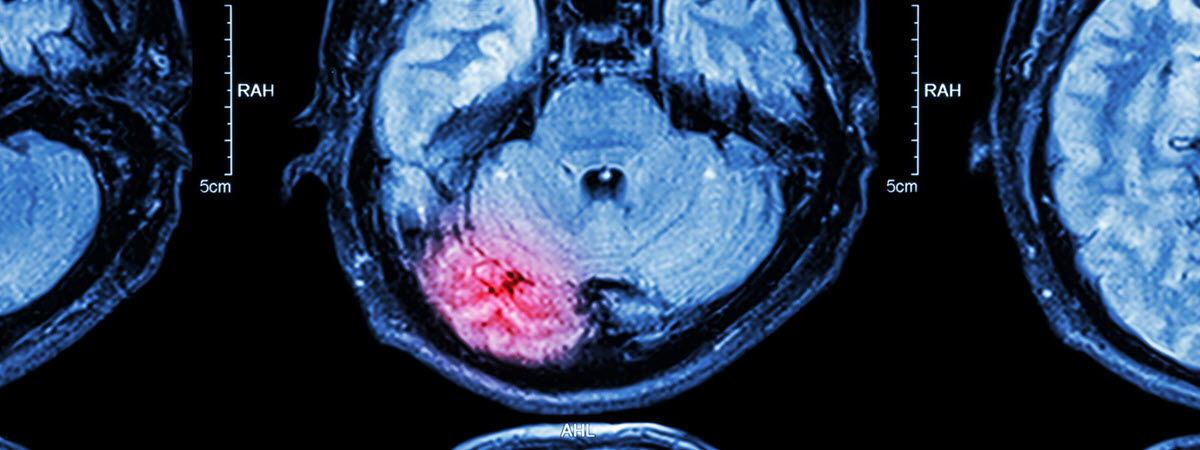

• Lesion on the intracranial area